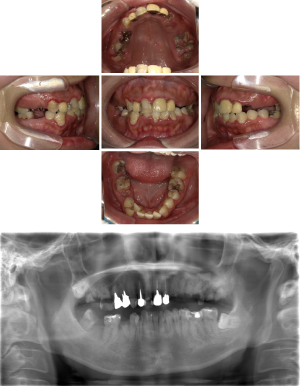

50代 インプラント治療(右上3左上3のみGBR)

| 年代・性別 | 50代・男性 |

| 主訴 | 入れ歯が合わず毎日ヨーグルトしか食べることができないので、しっかり咬めるインプラントにしたい。 |

| 部位 | 右下⑦⑥5④ 上顎③2①①2③ 左下67 |

| 治療期間 | 約9ヶ月 |

| 費用 | ¥4,273,500(税込) |

| 副作用・リスク |

|